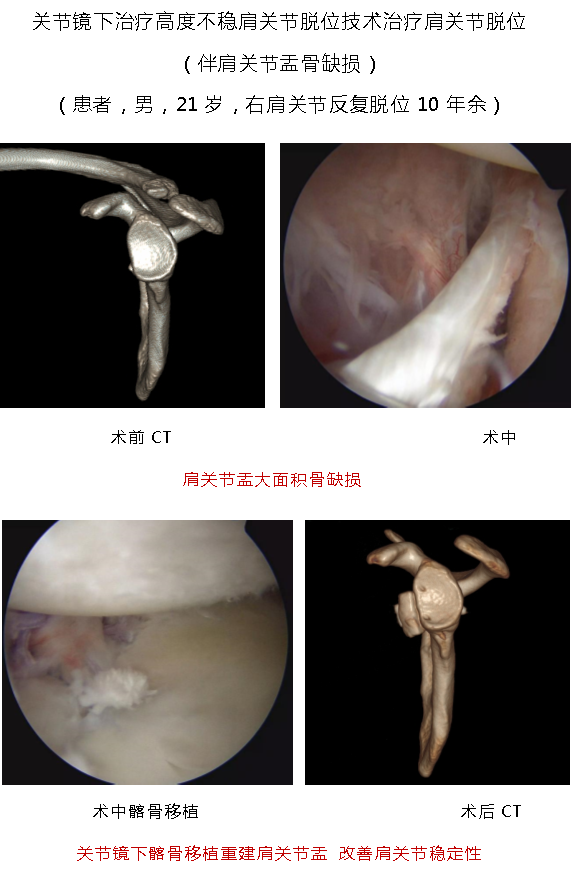

1.国际前沿的微创诊疗技术体系:科室聚焦肩、肘、髋、膝、踝多关节运动损伤,以 “精准化、个体化” 为核心,突破多项关键技术。膝关节领域:建立分龄化治疗方案 —— 青少年 “骨骺保护型前交叉韧带重建” 规避生长发育风险,成人 “联合前外侧韧带加强术” 提升术后稳定性,技术成熟度获行业广泛认可; 肩关节领域:个性化修复肩关节盂唇损伤、肩袖损伤,助力患者回归正常生活、重返运动;髋关节领域:为国内较早开展 “由外到内入路” 髋关节镜技术的科室之一,显著提升手术视野清晰度与操作安全性,年手术量超 300 台,居广东省前列。

3.核心业务范围:科室覆盖多关节运动损伤微创诊疗,主要包括:膝关节:前后交叉韧带重建、多韧带重建、半月板成形 / 修补 / 移植、髌股关节稳定术、关节软骨移植与修补、关节内游离体摘除;肩关节:肩袖撕裂关节镜下修补术、肩关节不稳关节镜下修复术(含 Laterjet 手术)、冻结肩关节镜下松解术、肩峰关节镜下减压成形术、SLAP 损伤修补术、肱二头肌腱固定术;髋关节:盂唇修补、股髋撞击症微创治疗、关节内游离体摘除;踝关节:踝关节不稳矫正、踝关节骨软骨损伤微创及开放治疗、跟腱腱病和断裂的微创及开放治疗、关节镜下各类踝关节疾病的微创治疗;肘关节:肘关节清理、网球肘、肘关节不稳、韧带重建;肘关节:腕关节清理、腕关节三角软骨损伤、腕关节不稳。